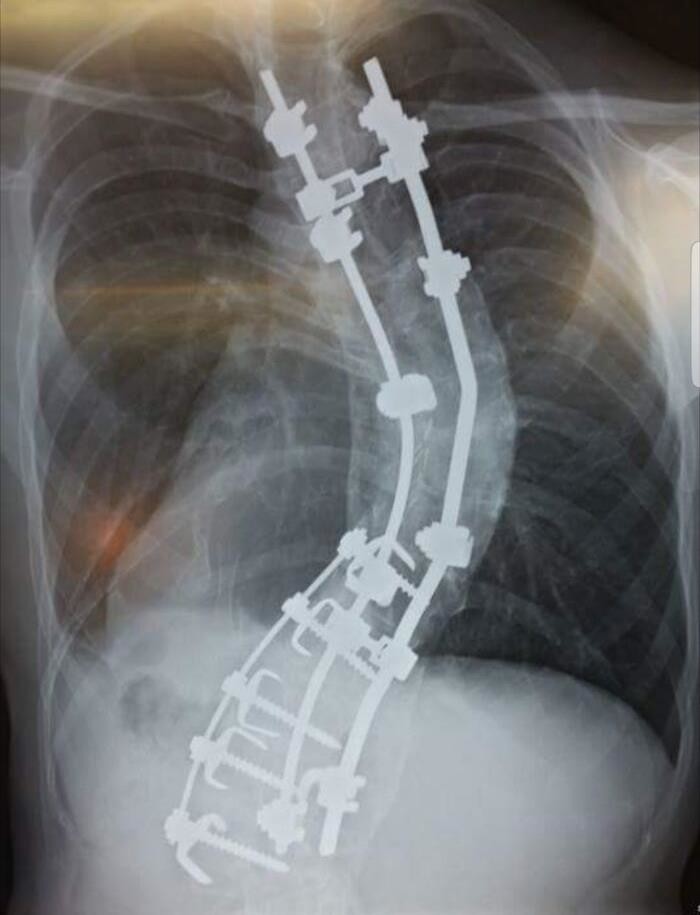

24. "Мой позвоночник. Мой рост был 178 см, когда я ложился под нож, теперь мой рост 188 см. А изначально должен был быть 2 метра"